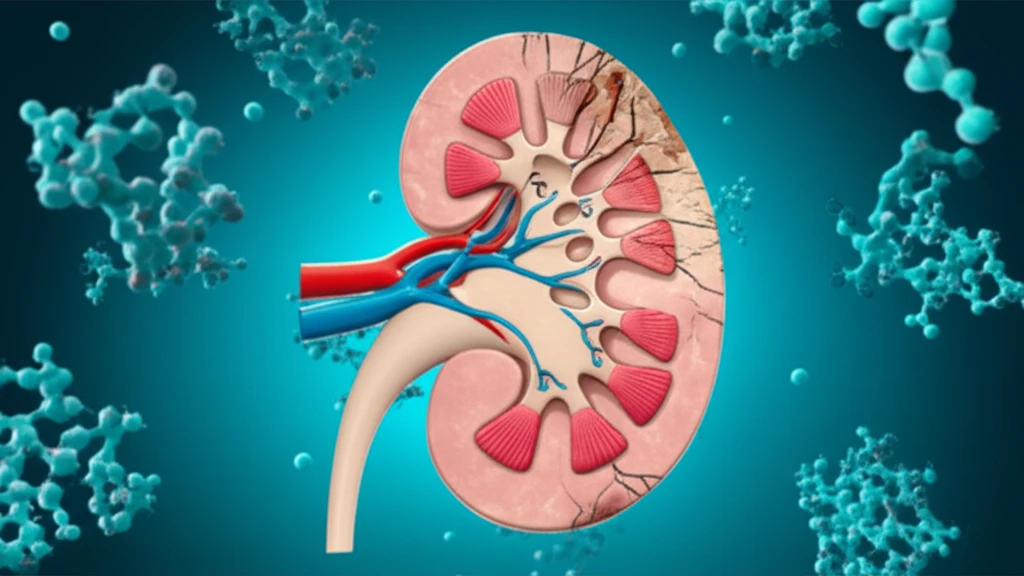

In 2018, end-stage renal disease (ESRD) affected over 700,000 individuals in the US, with nearly 500,000 relying on maintenance dialysis. Despite medical advancements, ESRD significantly increases the risk of death, especially from cardiovascular causes, highlighting the need to explore novel risk factors beyond traditional ones like hypertension and atherosclerosis.

One such factor is protein carbamylation, a posttranslational modification driven by cyanate, a byproduct of urea. While normally present in low concentrations, urea levels—and consequently cyanate and carbamylation—rise when kidney function declines. This process isn't solely linked to urea; factors like free amino acid levels, inflammation, diet, smoking, and environmental pollutants also play a role, contributing to molecular and cellular dysfunction.

This article delves into the consequences of protein carbamylation, particularly in the context of ESRD, and explores potential therapeutic strategies. Understanding this process is crucial to improving outcomes for individuals with kidney disease.